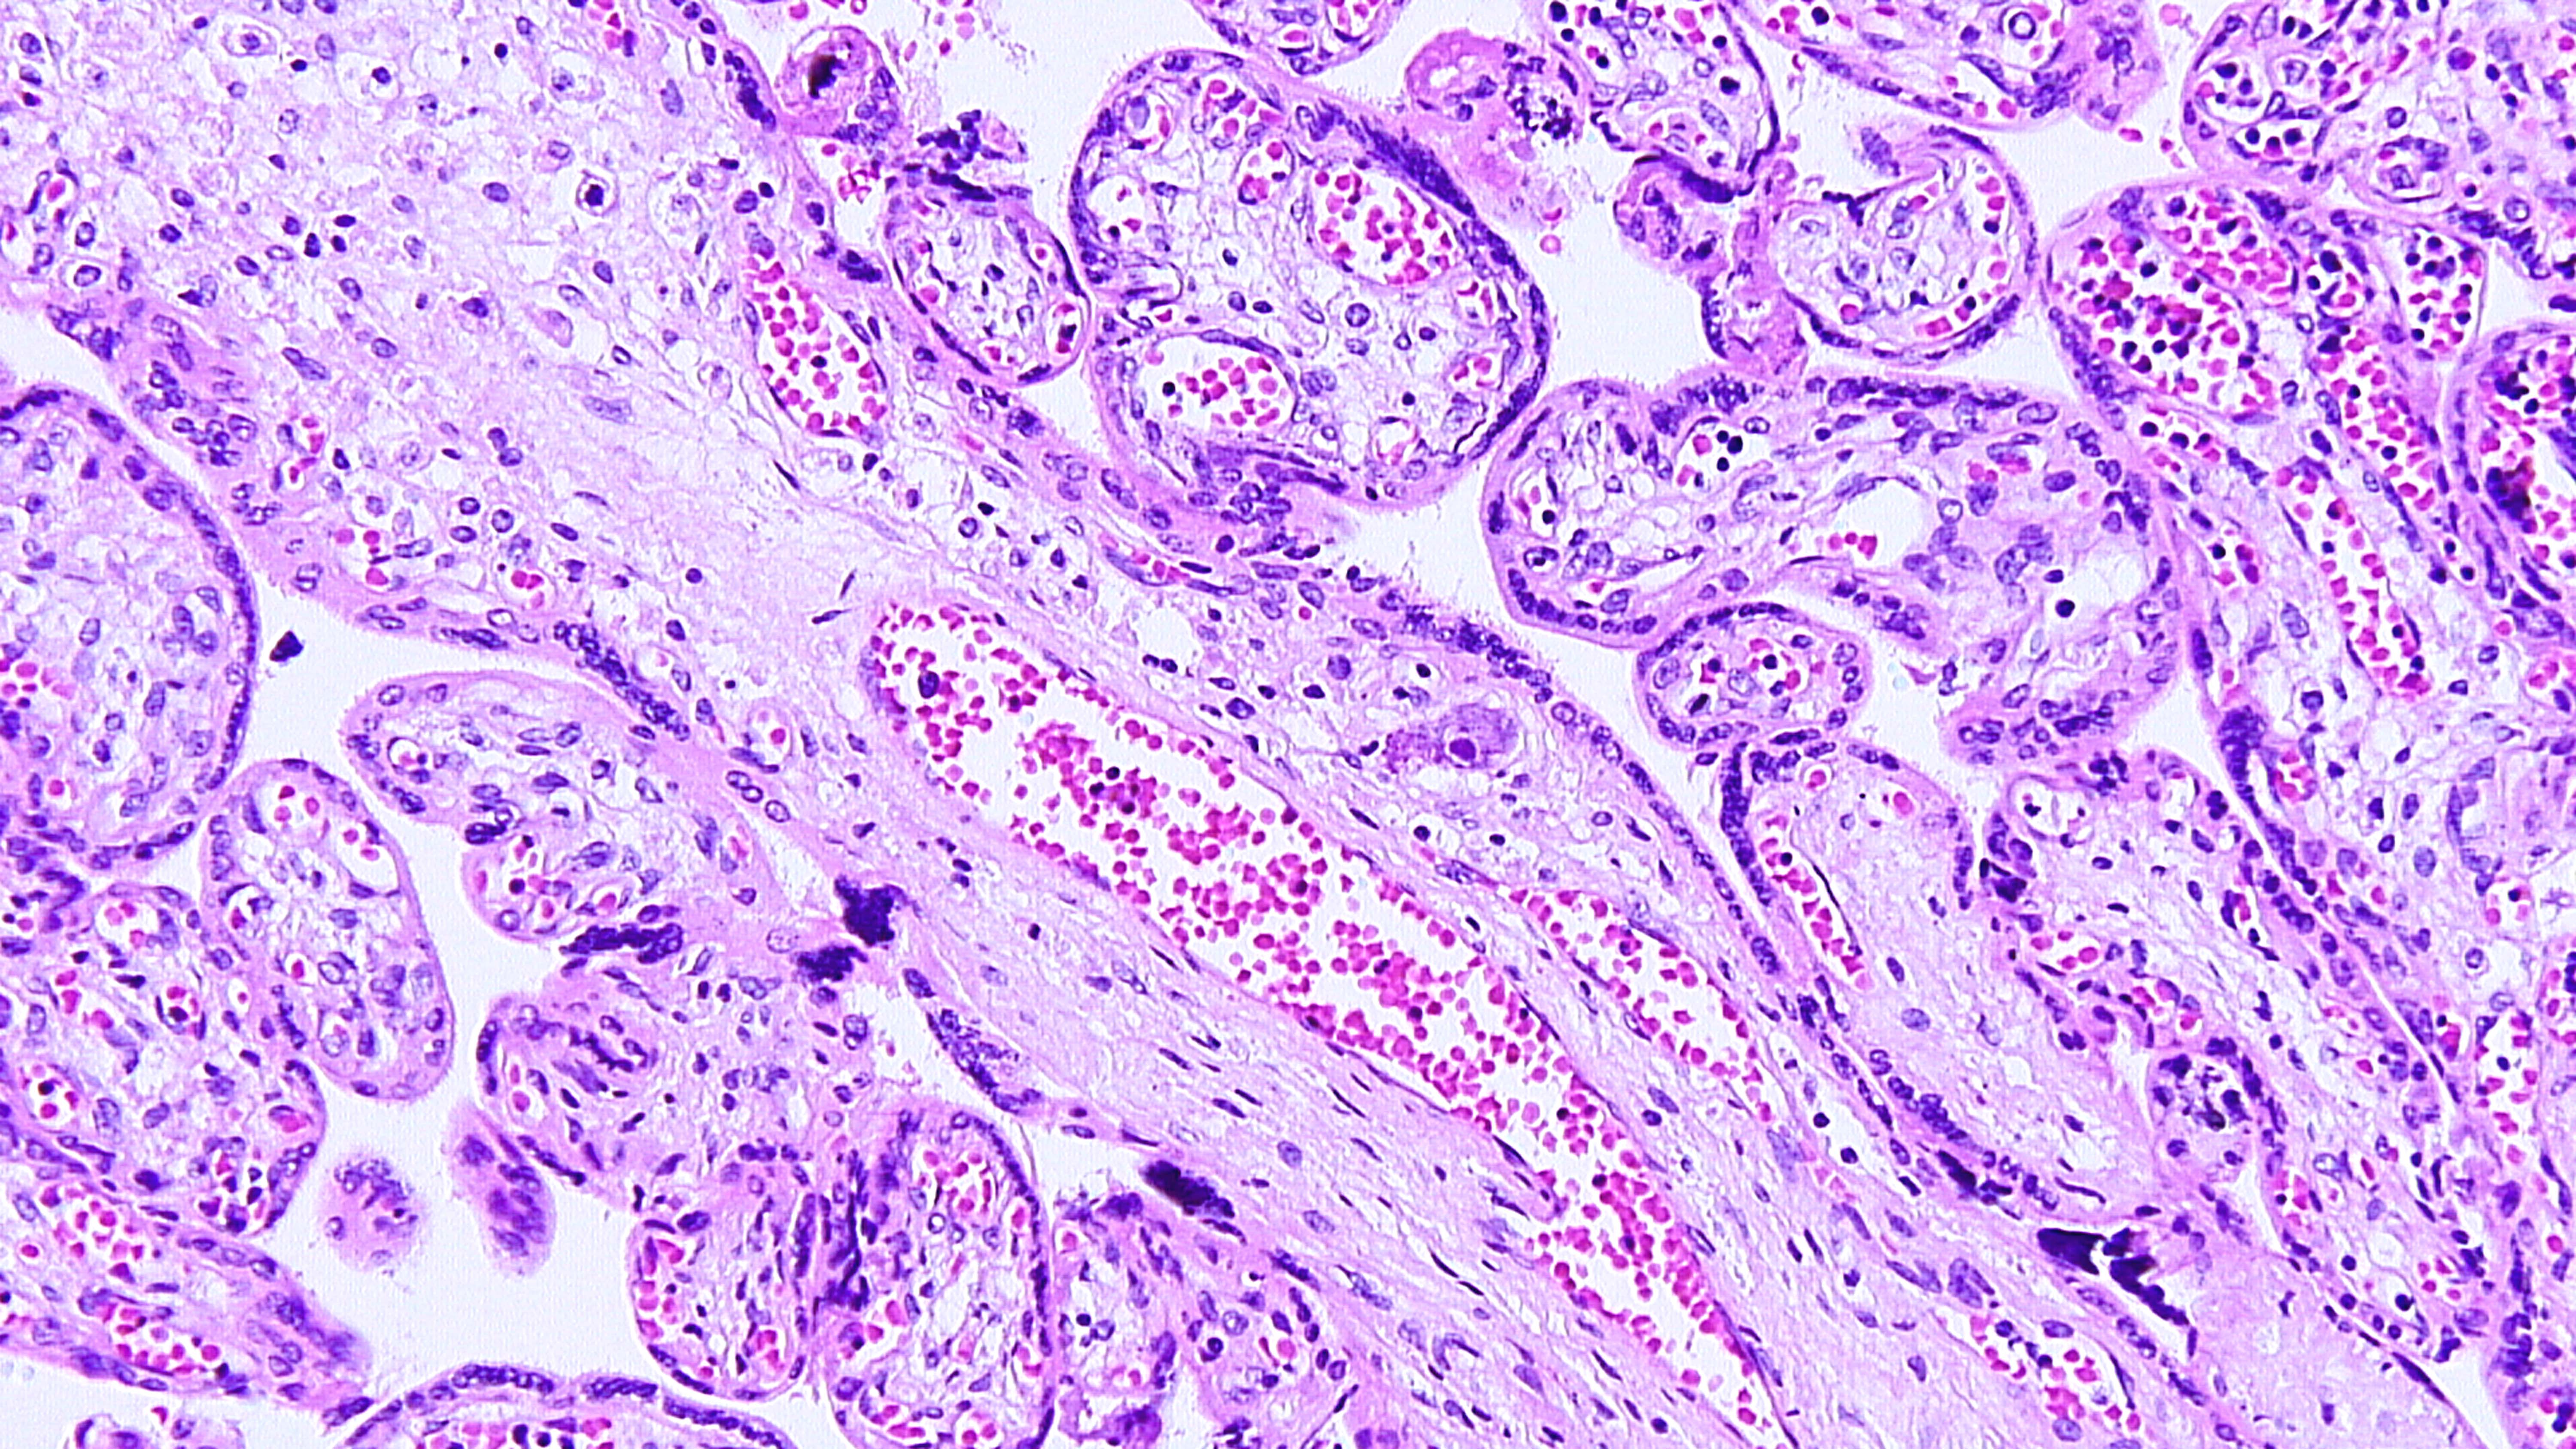

17-year-old primigravida with delivery of live born infant at 31 weeks...